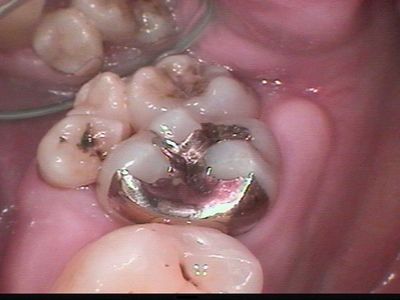

ところが、数か月前、虫歯治療に来院した患者さんには、10番の歯があったのでびっくりでした。

別に症候群を持った人でもなくごくごく普通の人なんです。

「初めて診せてもらいました。」なんて言ったらびっくりされそうだったので、それとなく記念に写真を撮らせてもらいました。

くわしくは解説しませんが10番があるんです!